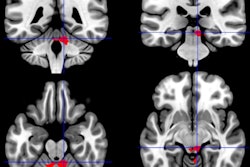

Reconstructed MR image shows the right arcuate (blue tracks and arrows) and inferior longitudinal fasciculus (ILF) (yellow tracks and arrows) in a representative subject. The track profile is colored according to fractional anisotropy, showing that the maximal increase in fractional anisotropy is in the anterior arcuate and ILF. The red, blue, and green spheres correspond to size and locations of increased cortical thickness in the right occipital, precentral, and middle temporal regions, respectively. The green arrows also point to the middle temporal region of increased thickness. Image courtesy of RSNA."Finding that the white-matter tract had abnormal fractional anisotropy and finding that those two end points of the tract had abnormal thickness suggest that something is going on in the right hemisphere [of the brain] in these chronic fatigue syndrome patients," Zeineh said.